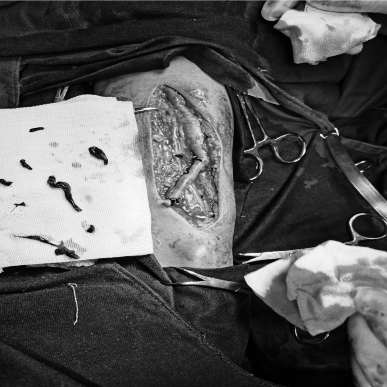

对于长期做透析的朋友来说,血管通路就是“生命线”,这条“路”一旦堵了(比如狭窄、长血栓),透析效果会变差,严重的还可能危及生命。以前遇到这种情况,不少人担心要“开大刀”,现在有了更简单的办法。 贵州航天医院肾脏风湿科开展了一项微创技术——血管通路介入治疗(用一根细针、一根微导管,顺着血管把堵塞的地方“疏通”开),不用大切口,也能解决内瘘狭窄、血栓、闭塞这些麻烦事。 这项技术是怎么做的? 医生在影像设备(彩超、DSA)的实时引导下,从皮肤上扎一个小针眼,把导管送到血管病变的位置,然后用球囊撑开狭窄的地方、或者溶掉血栓、必要时放个小支架,整个过程创伤小、恢复快、还能反复做。 主要能解决哪些问题? ※动静脉内瘘狭窄或闭塞:做球囊扩张术(PTA),是目前首选的办法。 ※内瘘里长了血栓同时伴有狭窄:溶栓+球囊扩张。 ※中心静脉(比如胸口附近的血管)狭窄或闭塞:球囊扩张或放支架。 ※需要放透析长期导管但位置不好放:精准置管。 哪些人适合做? 1.透析时血流量不够、静脉压力高、穿刺越来越困难。 2.彩超检查发现内瘘狭窄超过50%,或者内瘘发育不好、术后又窄了。 3.内瘘完全堵死,想尽量保住原来的血管。 4.手臂或脸肿了,可能是中心静脉堵了。 5.自身血管条件差,反复置管失败,或者身体受不了开刀手术。 6.目前脖子上或大腿上带着长期透析管,想拔掉管子改用自己的内瘘。 这项技术好在哪? ☑微创损伤小:就一个小针眼,几乎不留疤,局部麻醉就行,对身体影响小。 ☑看得清,打得准:彩超或DSA实时引导,医生能清楚看到血管,避开重要部位。 ☑恢复快:多数患者做完手术当天就能下床活动,内瘘很快就能再用上,不用等。 ☑省着用血管:球囊扩张可以反复做,尽量保住自己的血管。 ☑能重复治疗:以后万一再堵了,还可以再做介入,不用“一刀切”重新建一条通路。 ☑减少感染风险:成功救回内瘘后,很多患者可以拔掉临时或长期的透析导管,感染风险更低,也保护了中心静脉。 透析小常识: 1.透析就是帮助受损的肾脏“洗血”,清除体内多余水分和代谢废物,多数人每周做2-3次,每次约4小时。 2.内瘘是透析患者手臂上通过手术将动脉和静脉连接起来的一种血管通路,摸上去会有“嗡嗡”的震颤感,是透析治疗的关键通道,平时要护好内瘘——每天用手摸一摸震颤是否正常,别压着内瘘侧手臂睡觉,不提重物,不在这侧抽血或量血压。 3.饮食上注意少喝水(两次透析间体重增长不超过干体重的3%-5%),少吃盐和含磷高的食物(如坚果、动物内脏、可乐),适当吃鸡蛋、瘦肉、鱼肉等优质蛋白。 4.如果发现内瘘震颤变弱或消失、手臂肿胀、透析时血流量不足,立即告诉医生。 注:部分图片来源于网络,如有侵权,请联系删除。 贵州航天医院 肾脏风湿科专家简介 冯远军 肾脏风湿、肝胆外科党支部书记,肾脏风湿科主任,主任医师 临床擅长:对慢性肾脏病、急性肾损伤、急慢性肾小球肾炎、肾病综合症、风湿性疾病、间质性肾炎、肾小管损伤等疾病的诊治及血液透析技术、动静脉内瘘成形术及疑难病例的诊治具有丰富的临床经验。 曾在上海市第一人民医院及贵阳市第一人民医院进修学习,贵州省医学会肾脏病学分会第五届委员会委员,遵义市医学会肾脏病学分会第一届委员会副主任委员,遵义市医学会风湿病学分会第一届委员会副主任委员,荣获“贵州航天劳动模范、遵义市汇川区先进工作者”,遵义市医疗事故鉴定专家库成员,主持省市级科研项目4项,完成4项,近5年发表论文10余篇,北大核心期刊1篇。 王卫华 肾脏风湿科主任医师 临床擅长:从事临床工作28年,擅长尿毒症患者血管通路的建设及维护(如标准和高位动静脉内瘘术、取栓+内瘘重建术、内瘘狭窄球囊扩张术、长期中心静脉置管术及肾穿刺活检术)等手术,对原发性和继发性肾病综合征、急、慢性肾小球肾炎、慢性肾脏病、泌尿系感染、结缔组织病、急性中毒、痛风、贫血、血小板减少症等疾病诊治及血液透析技术应用等具有丰富的临床经验。 1995年毕业于遵义医学院临床医学系,曾前往重庆医科大学进修学习肾脏疾病及血液净化,遵义市医学会肾脏病学分会常务委员,遵义市血液净化质量控制中心委员,先后发表肾病专业省部级医学刊物医学论文8篇,主持市级科研项目2项。 李丽华 中共党员,肾脏风湿科副主任医师 临床擅长:从事临床工作17年,对慢性肾脏病、急性肾损伤、急慢性肾小球肾炎、肾病综合征、风湿性疾病、间质性肾炎、肾小管损伤、急慢性肾衰竭的血液透析、CRRT治疗以及血管通路的建设维护等具有丰富的临床诊疗经验。 2006年毕业于遵义医学院临床专业,曾在遵义医学院附属医院完成住院医生规范化培养,并前往第三军医大学新桥医院、珠海市人民医院进修学习,中华医学会遵义市肾脏病学分会委员,遵义中医药学会肾病专业委员会委员,遵义市血液净化质量控制中心委员,遵义市医学会血液学分会委员会委员,发表省部级医学刊物医学论文4篇,主持参与省级科研课题1项,主持参与市级科研课题1项,院级新技术6项,获得本专业授权实用新型专利3项。 李 玫 中共党员,肾脏风湿科副主任医师 临床擅长:从事临床工作15年,对慢性肾脏病、急性肾损伤、急慢性肾小球肾炎、肾病综合征、风湿性疾病、间质性肾炎、肾小管损伤等疾病的诊治具有丰富的临床经验,擅长血液透析技术、动静脉内瘘成形术等。 2008年毕业于遵义医学院临床医学系,曾前往遵义医学院附属医院进修学习肾脏病与血液净化相关技术,遵义市医学会肾脏病学分会委员,发表肾病专业省部级医学刊物医学论文4篇。 贵州航天医院肾脏风湿科简介 • ✦ 基本情况 ✦ • 贵州航天医院肾脏风湿科2017年建立,住院患者承载能力达到50人左右,透析治疗服务惠及280余人的患者群体,在学科建设、高端医疗设备引进及专业技术队伍已达到区域内领先水平。科室共有医护人员46名,副高级以上专家7名,亚专业设置齐全,涵盖肾脏疾病、风湿免疫疾病药物治疗、透析治疗及透析通路维护等多个专业领域,为患者提供全面的诊疗服务。配备了尖端的医疗设备与智能化的辅助系统,包括透析机、CRRT机等设备。 • ✦ 专科特色 ✦ • (一)肾脏病治疗领域:专精于血液透析、血液透析滤过、血液灌流、血浆置换、CRRT等尖端技术,致力于为患者量身打造个性化的肾脏替代治疗方案。 (二)在风湿病治疗方面:凭借生物制剂、免疫抑制剂等前沿药物,结合患者的具体情况,精心策划个体化的治疗策略,有效减轻患者症状,显著提升生活质量。 (三)超声引导下球囊扩张术:内瘘狭窄是内瘘最常见的并发症之一,我们采用超声引导下球囊扩张术,通过微创方式恢复内瘘通畅,有效避免了传统手术带来的创伤和痛苦。 (四)内瘘血栓溶栓治疗、取栓术:血栓形成是内瘘功能丧失的主要原因之一,根据患者具体情况,采用溶栓治疗、取栓术等多种手段,确保患者及时恢复透析治疗。 (五)内瘘动脉瘤形成治疗:动脉瘤是由于内瘘局部血流动力学改变引起的血管扩张性疾病,采取佩戴弹力绷带、手术修复等措施,防止动脉瘤进一步发展和破裂。 (六)内瘘感染治疗:内瘘感染是内瘘并发症中最为严重的类型之一,一般采用敏感抗生素进行抗感染治疗,严重者采取手术清创等措施。 (七)内瘘窃血综合征治疗:是由于内瘘建立后,远端肢体血流减少引起的一系列症状,通过调整透析方案、改善内瘘血流分布及必要时重建内瘘等措施,有效缓解患者的症状并提高其生活质量。 • ✦ 诊疗范围 ✦ • 擅长治疗急慢性肾炎、肾病综合征、肾衰竭等肾脏疾病;擅长治疗类风湿关节炎、系统性红斑狼疮、干燥综合征等风湿免疫性疾病,并为患者提供健康教育与康复指导,帮助患者更好地管理疾病,提高生活质量。 end